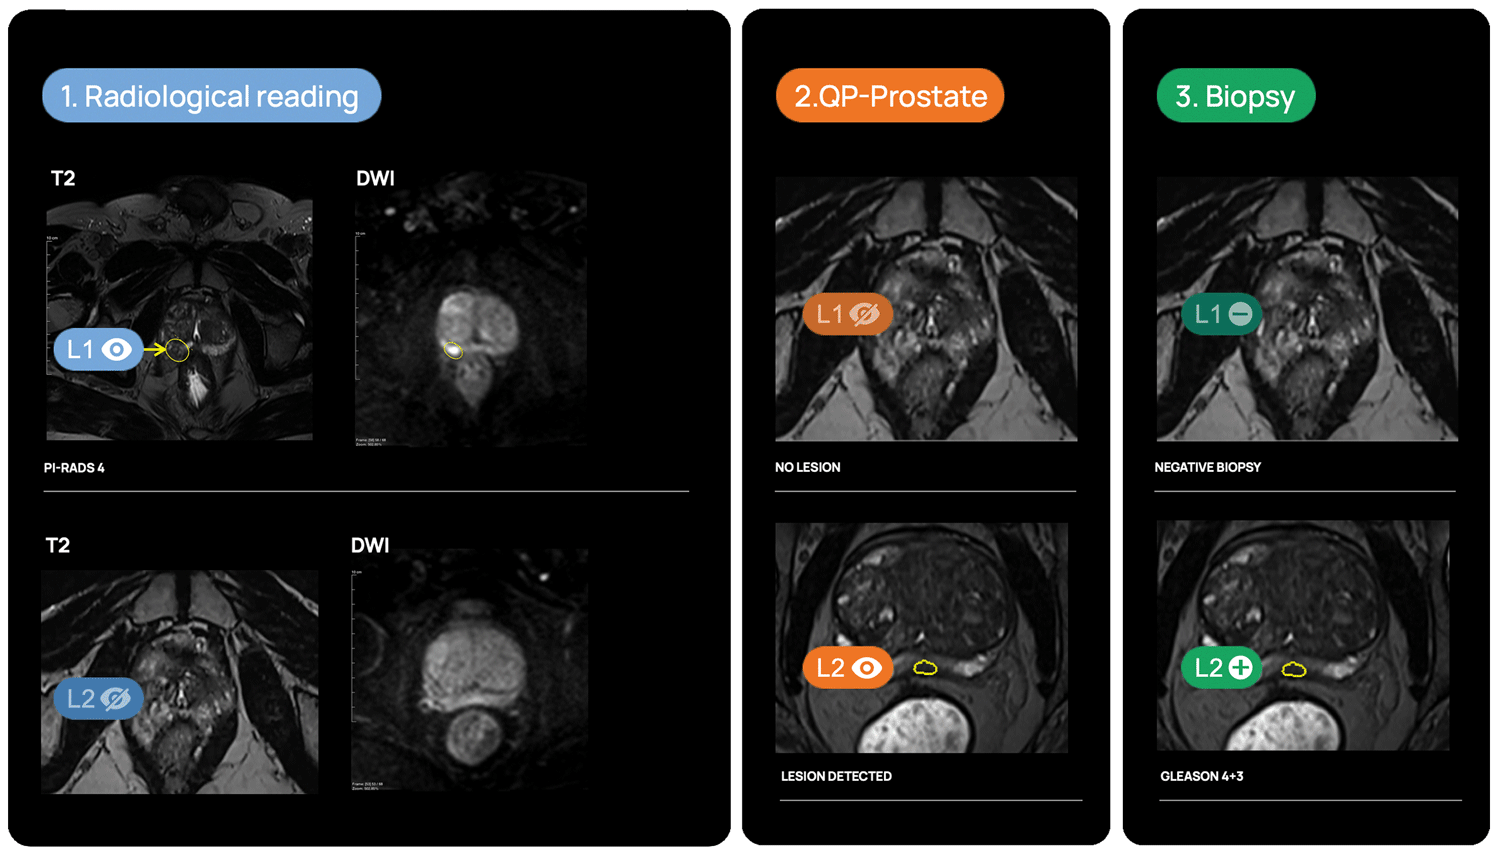

QP-Prostate is setting a new standard for accuracy, speed, and diagnostic precision. Its AI algorithm identifies and stratifies by likelihood intermediate and high-grade aggressive prostate cancer lesions, and provides a segmentation of the prostate. This allows Health Care Professionals to improve their diagnostic accuracy and fusion biopsy planning.

Lesion detection & diagnosis

QP-Prostate automatically identifies and highlights prostate regions suspicious for aggressive prostate cancer, assigning each a confidence-based classification score.

Fusion biopsy planning

QP-Prostate is fully integrated into most of the fusión biopsy devices, to allow a more accurate targeted biopsy.